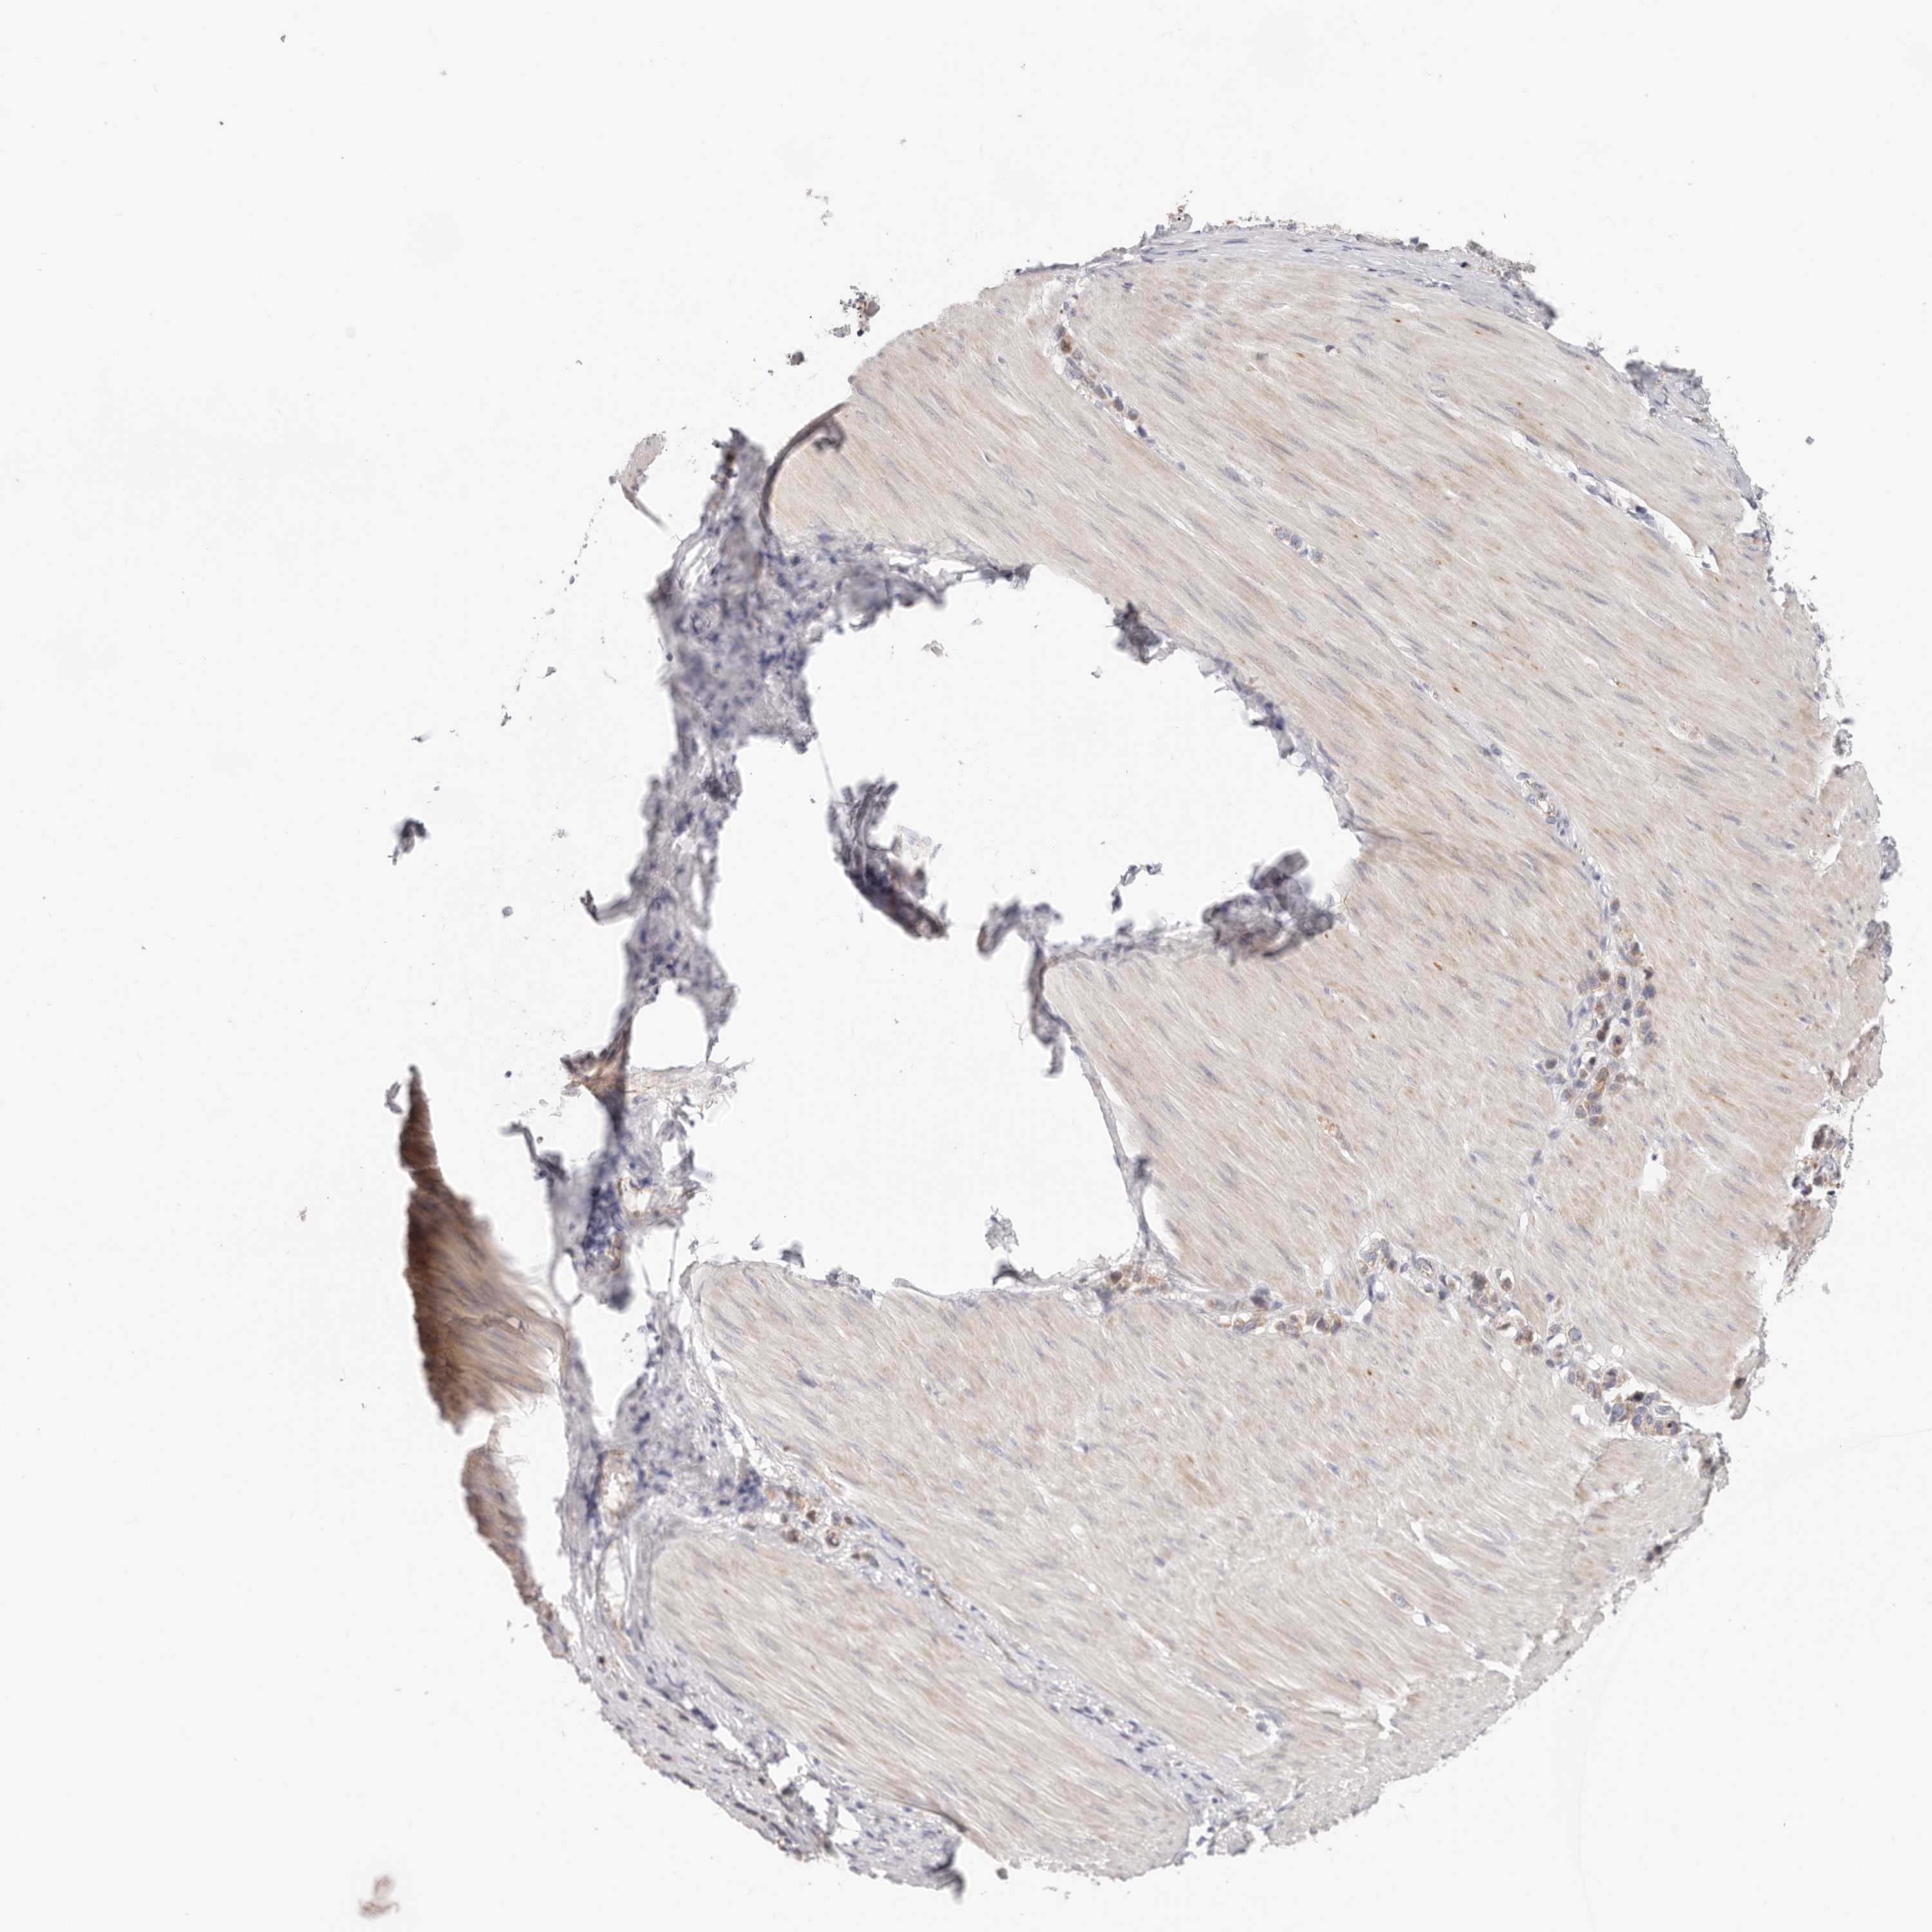

STOMACH CANCER - Protein expressioni

A mouse-over function shows sample information and annotation data. Click on an image to view it in a full screen mode. Samples can be filtered based on level of antibody staining by selecting one or several of the following categories: high, medium, low and not detected. The assay and annotation is described here.

Note that samples used for immunohistochemistry by the Human Protein Atlas do not correspond to samples in the TCGA dataset.

Antibody stainingi

Antibody staining in the annotated cell types in the current human tissue is reported as not detected, low, medium, or high, based on conventional immunohistochemistry profiling in selected tissues. This score is based on the combination of the staining intensity and fraction of stained cells.

Each image is clickable and will lead to virtual microscopy that enables deeper exploration of all samples and also displays staining intensity scores, fraction scores and subcellular localization as well as patient and tissue information for each sample.

HPA030212

HPA030213

HPA030214

HPA030215

CAB013496

Adenocarcinoma, NOS